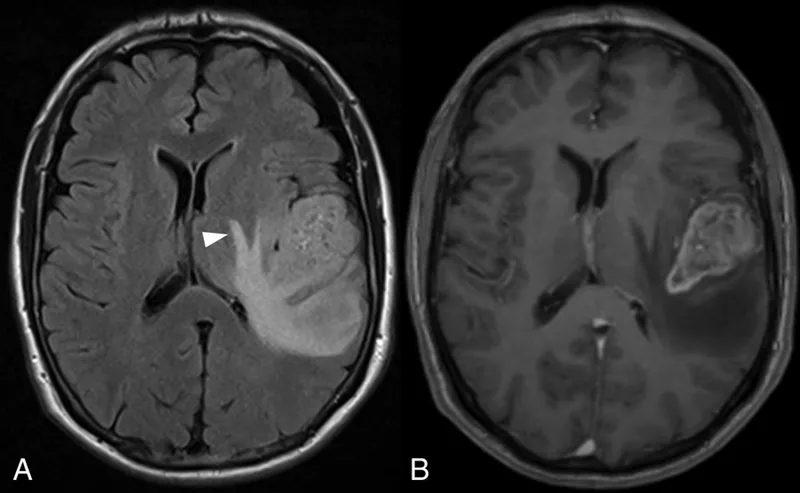

| Imaging Buzzwords | Butterfly glioma, ring-enhancing, central necrosis, peritumoral edema | Dural tail, homogeneously enhancing, extra-axial | Multiple, well-circumscribed, vasogenic edema | Snowman/figure-of-8 (suprasellar extension), sellar mass |

- Glioblastoma (GBM): Most common adult primary; butterfly glioma appearance.